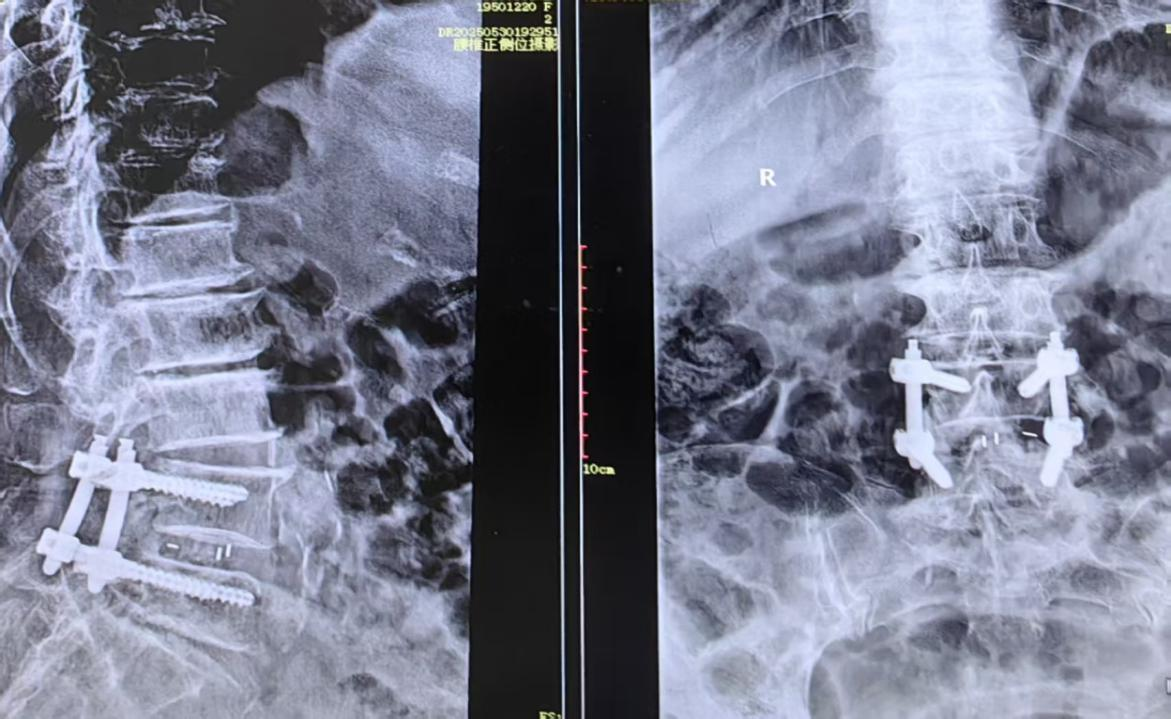

术中医生操作画面及患者术后DR片,椎体滑脱完全纠正,重建脊柱序列性及稳定性